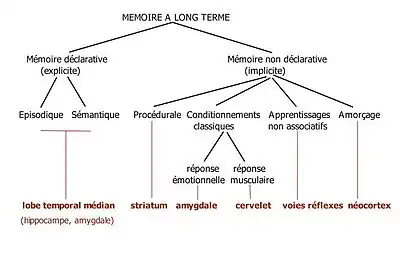

Il est maintenant bien établi qu'il existe plusieurs systèmes de mémoire contrôlés par des substrats neuronaux distincts et en interaction. On distingue dans la mémoire à long terme[33] :

- la mémoire non déclarative : elle recouvre différents types de mémorisation qui sont encore possibles chez les amnésiques. Il peut s'agir d'habiletés comme faire du vélo (mémoire procédurale), de conditionnements classiques pavloviens, de l'apprentissage non associatif (sensibilisation, habituation comme l'habituation au tic-tac d'une horloge) ou d'amorçage ;

- la mémoire déclarative : elle concerne des faits et événements qui peuvent être récupérés par un effort conscient et être décrits verbalement. Elle dépend essentiellement de l'intégrité de la formation hippocampique. Elle concerne soit des événements autobiographiques ancrés dans le temps et l'espace (mémoire épisodique) soit des concepts généraux (mémoire sémantique)

Implications de l'amygdale

L'amygdale intervient dans les systèmes de mémorisation là où l'émotion est impliquée. On la retrouve dans les deux systèmes[34] :

- dans le premier système, non déclaratif, l'amygdale est spécialisée dans le traitement des émotions principalement négatives. Elle joue un rôle essentiel dans le conditionnement classique aversif dans lequel un stimulus neutre est associé avec un événement désagréable (voir section précédente) ;

- dans le second système, déclaratif et contrôlé par le complexe hippocampique, elle renforce la rétention mnésique de la mémoire épisodique lorsque les souvenirs sont marqués par l'émotion.